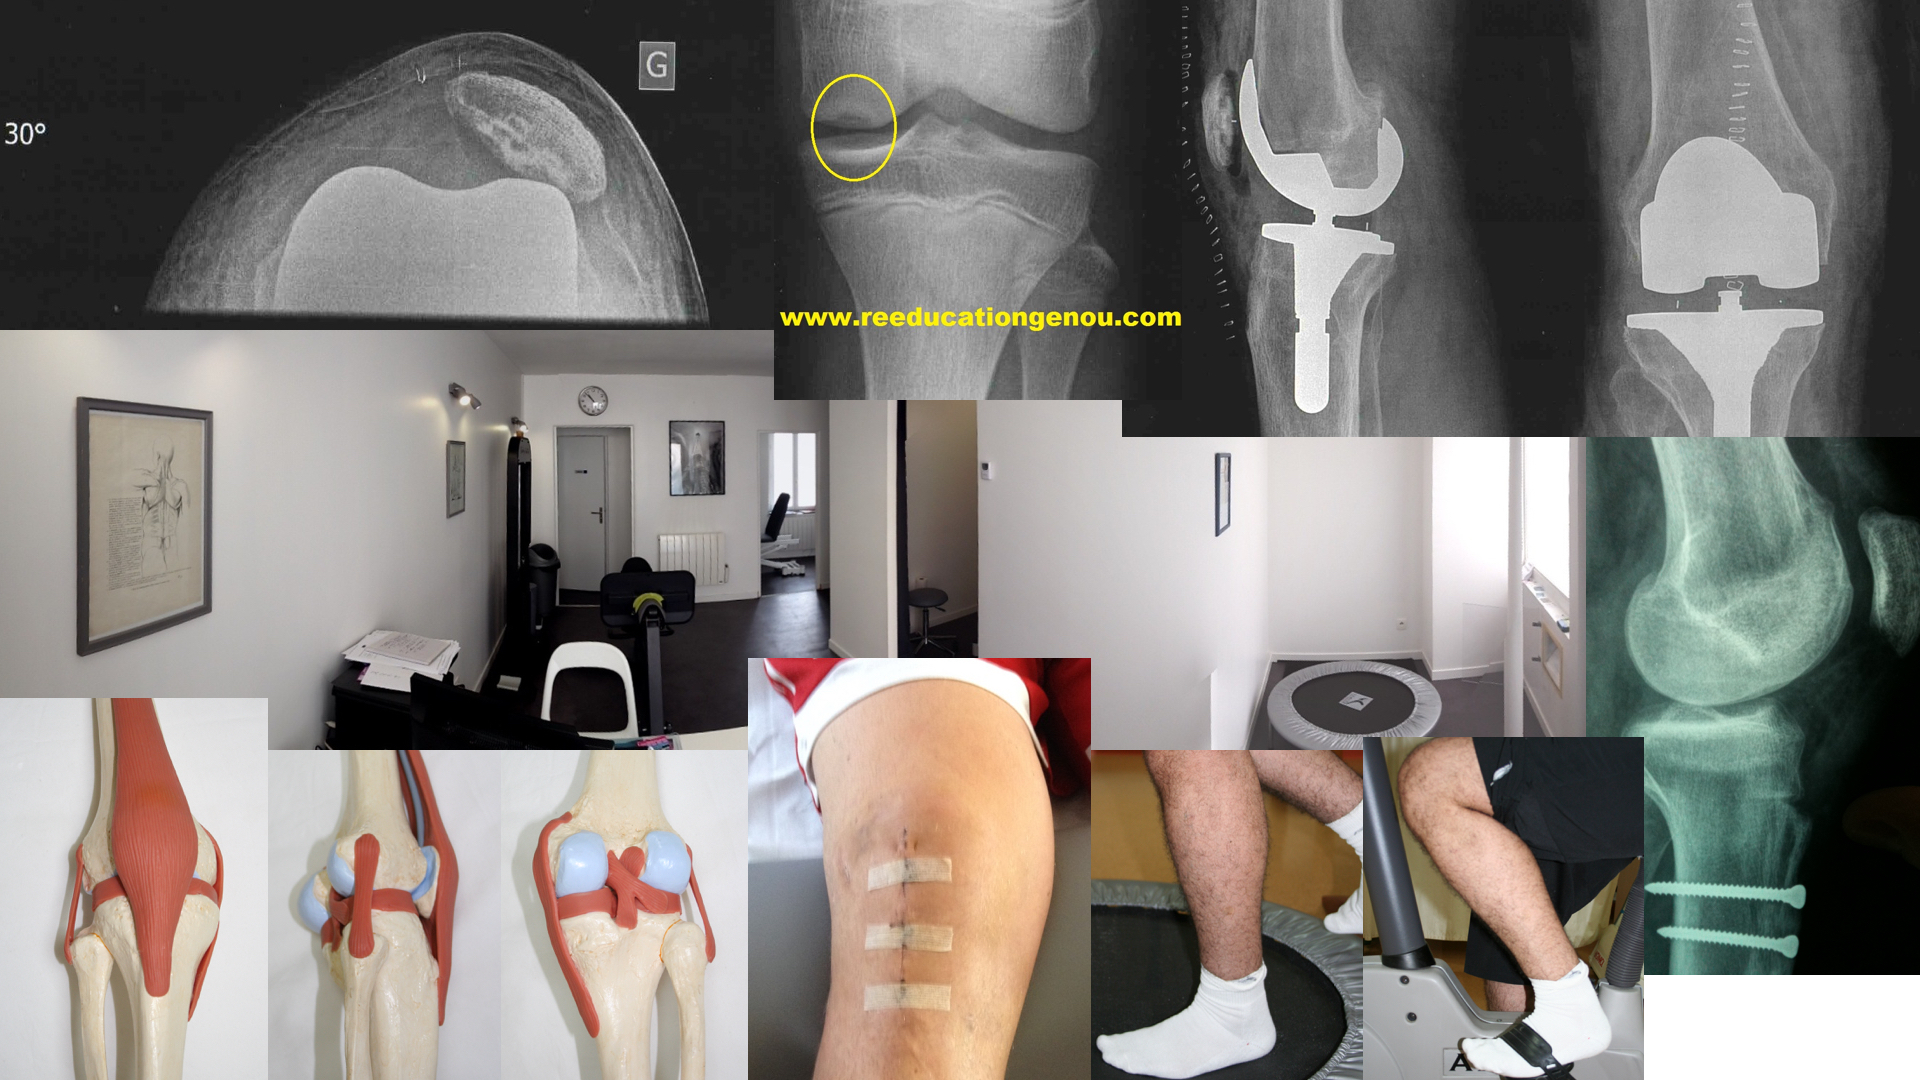

La rotule après une ligamentoplastie du LCA

LA ROTULE APRES LIGAMENTOPLASTIE ou simplement chirurgie du genou

Il n'y pas un genou ligamentaire ou opéré qui n'ait pas à un moment de sa rééducation pré ou post opératoire des douleurs rotuliennes...en route pour la description :